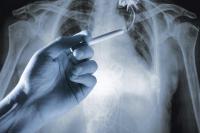

Half of Smokers with Normal Lung Function Have COPD-Like Symptoms

Half of smokers with normal lung function nevertheless have lung damage and symptoms of chronic obstructive lung disease (COPD), according to a study published online in New England Journal of Medicine. The findings suggest that smokers with respiratory symptoms in the absence of a COPD diagnosis may need more treatment than once thought.

COPD is defined as a chronic limitation in airflow in the lungs and is most often caused by smoking. It is the third leading cause of death in the United States and is diagnosed when the flow of air a patient can exhale into a device called a spirometer has dropped to a certain threshold, indicating airway obstruction. The diagnosis does not take into account the frequency or severity of symptoms such as shortness of breath, cough, or reduced exercise tolerance. Many smokers have these symptoms without meeting the definition required for a COPD diagnosis, says R. Graham Barr, MD, DrPH, professor of medicine at Columbia University’s College of Physicians and Surgeons and professor of epidemiology at Columbia’s Mailman School of Public Health.

About half of the smokers had COPD-like symptoms despite having normal spirometry readings. CT lung scans also revealed that many had thickening of the airways, which occurs in people with chronic bronchitis. Symptomatic smokers had more frequent respiratory illnesses or flare-ups that required the use of respiratory medications or medical attention, including hospitalization, than nonsmokers and nonsymptomatic smokers.